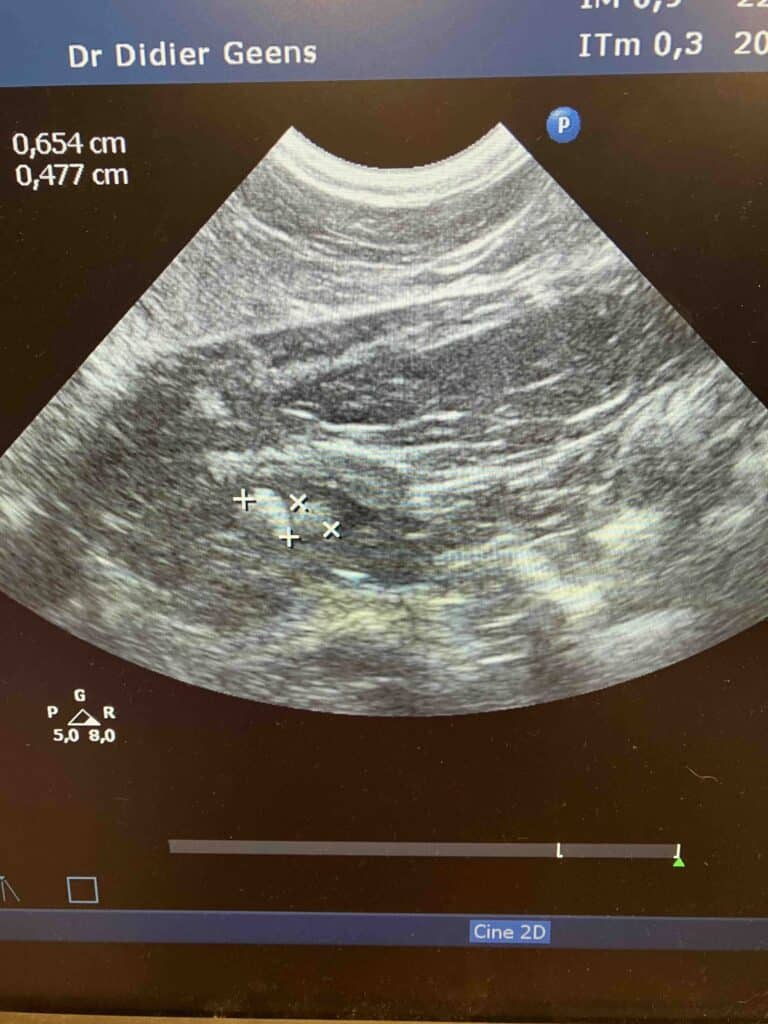

Echographie de la vessie d'un chat qui a des difficultés pour uriner. L'examen met en évidence une grande quantité de cristaux (sablose vésicale) dans la vessie